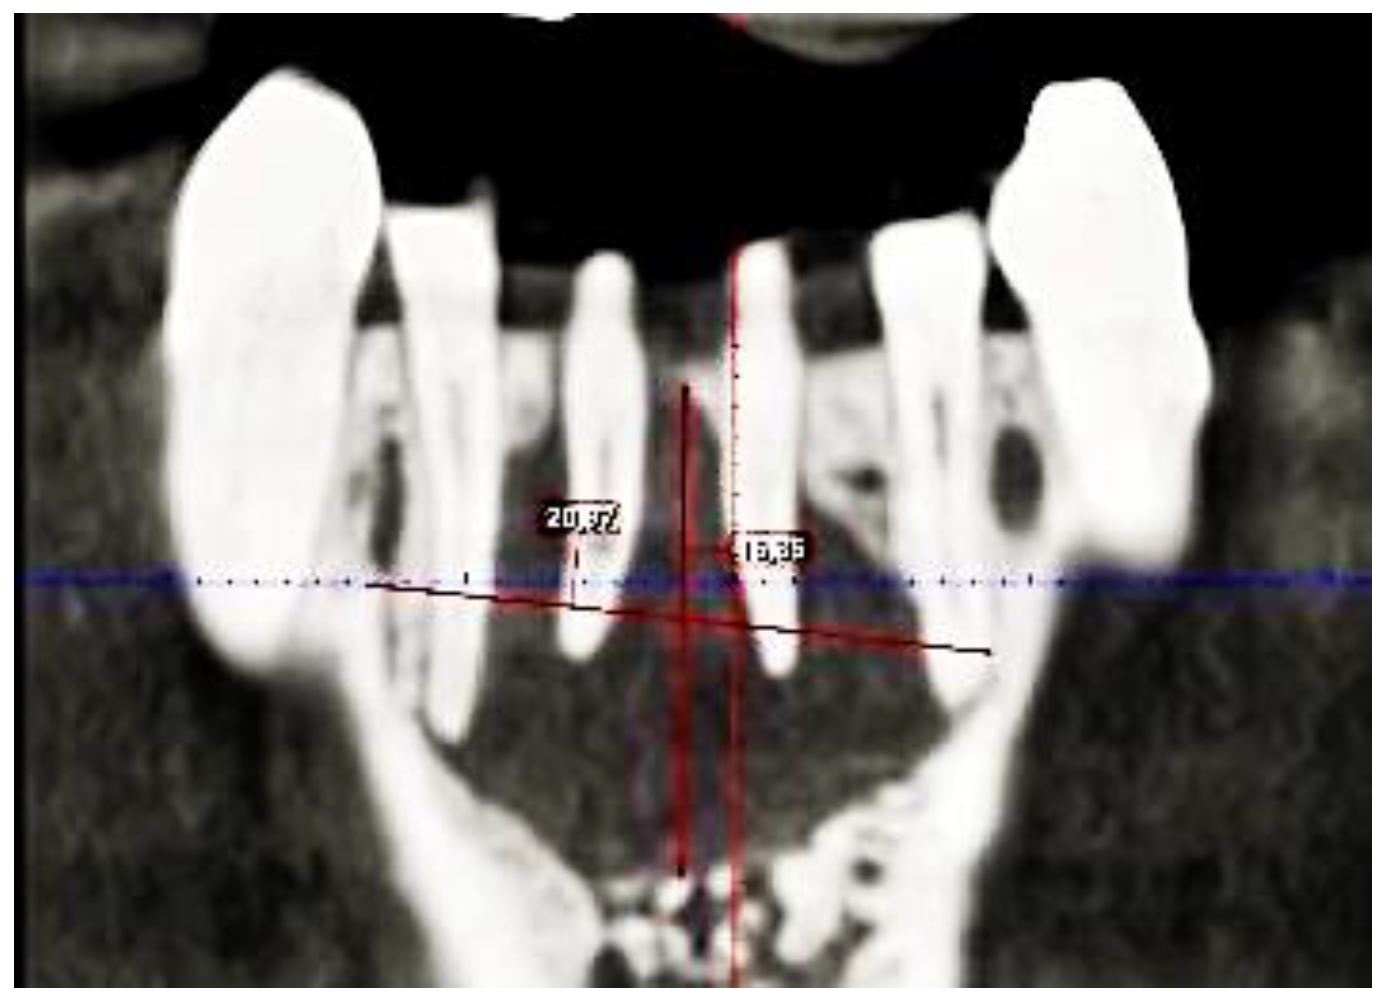

2. Case Description